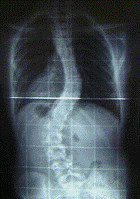

Хребет - це витончена структура, що збоку нагадує витягнуту букву «S».

Верхня частина спини нахилена назовні, а нижня частина спини злегка вигнута

всередину. Хоча якщо дивитися ззаду, хребет буде виглядати прямою лінією від

основи шиї до куприка. Сколіоз - це бічне викривлення хребта. Він з’являється й

розвивається в період інтенсивного зростання організму. Дитина росте не

зовнішніх ознак і симптомів сколіозу відносяться:

· Нерівне розташування плечей;

· Випирання кута однієї лопатки;

· Асиметрія талії;

· Асиметрія шкірних складок тулуба;

· Перекіс тазу;

· Нахил в один бік

Якщо кривизна сколіозу посилюється, хребет теж починає

скручуватися або згинатися, на додаток до бічного викривлення. Це призводить до

того, що ребра на одній стороні тіла випирають назовні, утворюючи реберний

горб. На іншому боці ж формується глибока западина, що разом деформує тулуб.

Важкий ступінь сколіозу може викликати біль у спині і утруднене дихання.